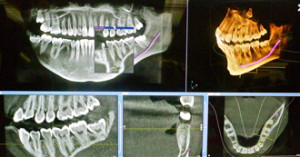

歯科用CT

コラム「歯科用CT」の画像